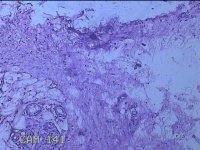

右侧拇指掌侧结节

性别

女

年龄

25岁

临床诊断

皮下结节

一般病史

发现右侧拇指结节2个月余。

标本名称

大体所见

灰白粉红色带皮肤样结节1.5x0.5x0.3cm一个,表面糜烂,切开结节呈实性,切面灰白粉红色,质软。